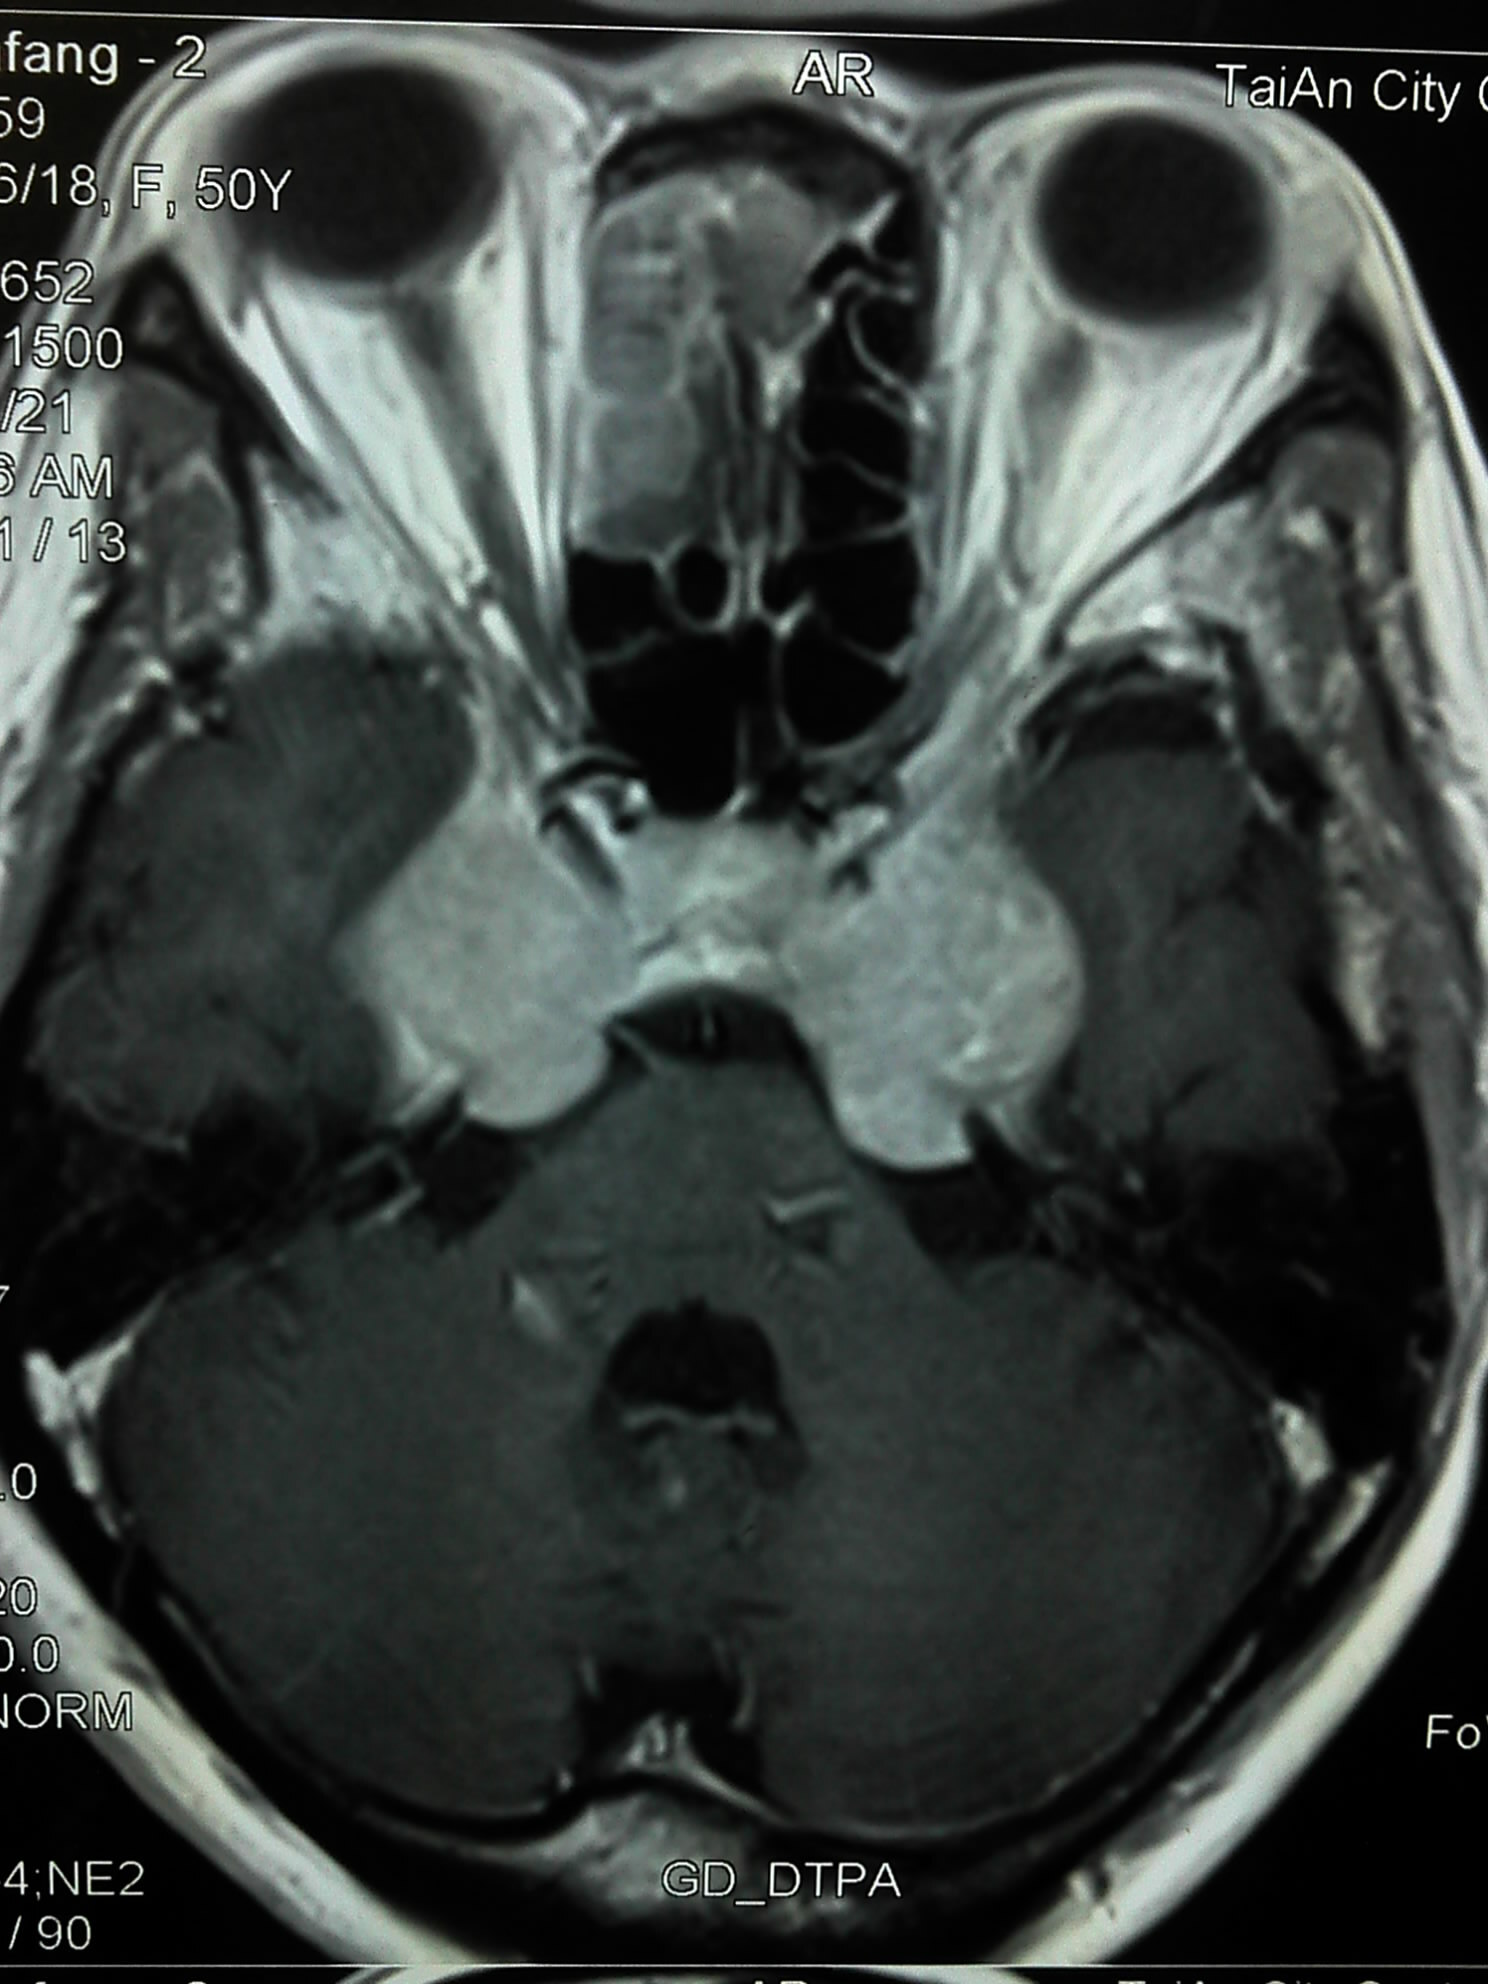

下面是病人的最早的影像资料: